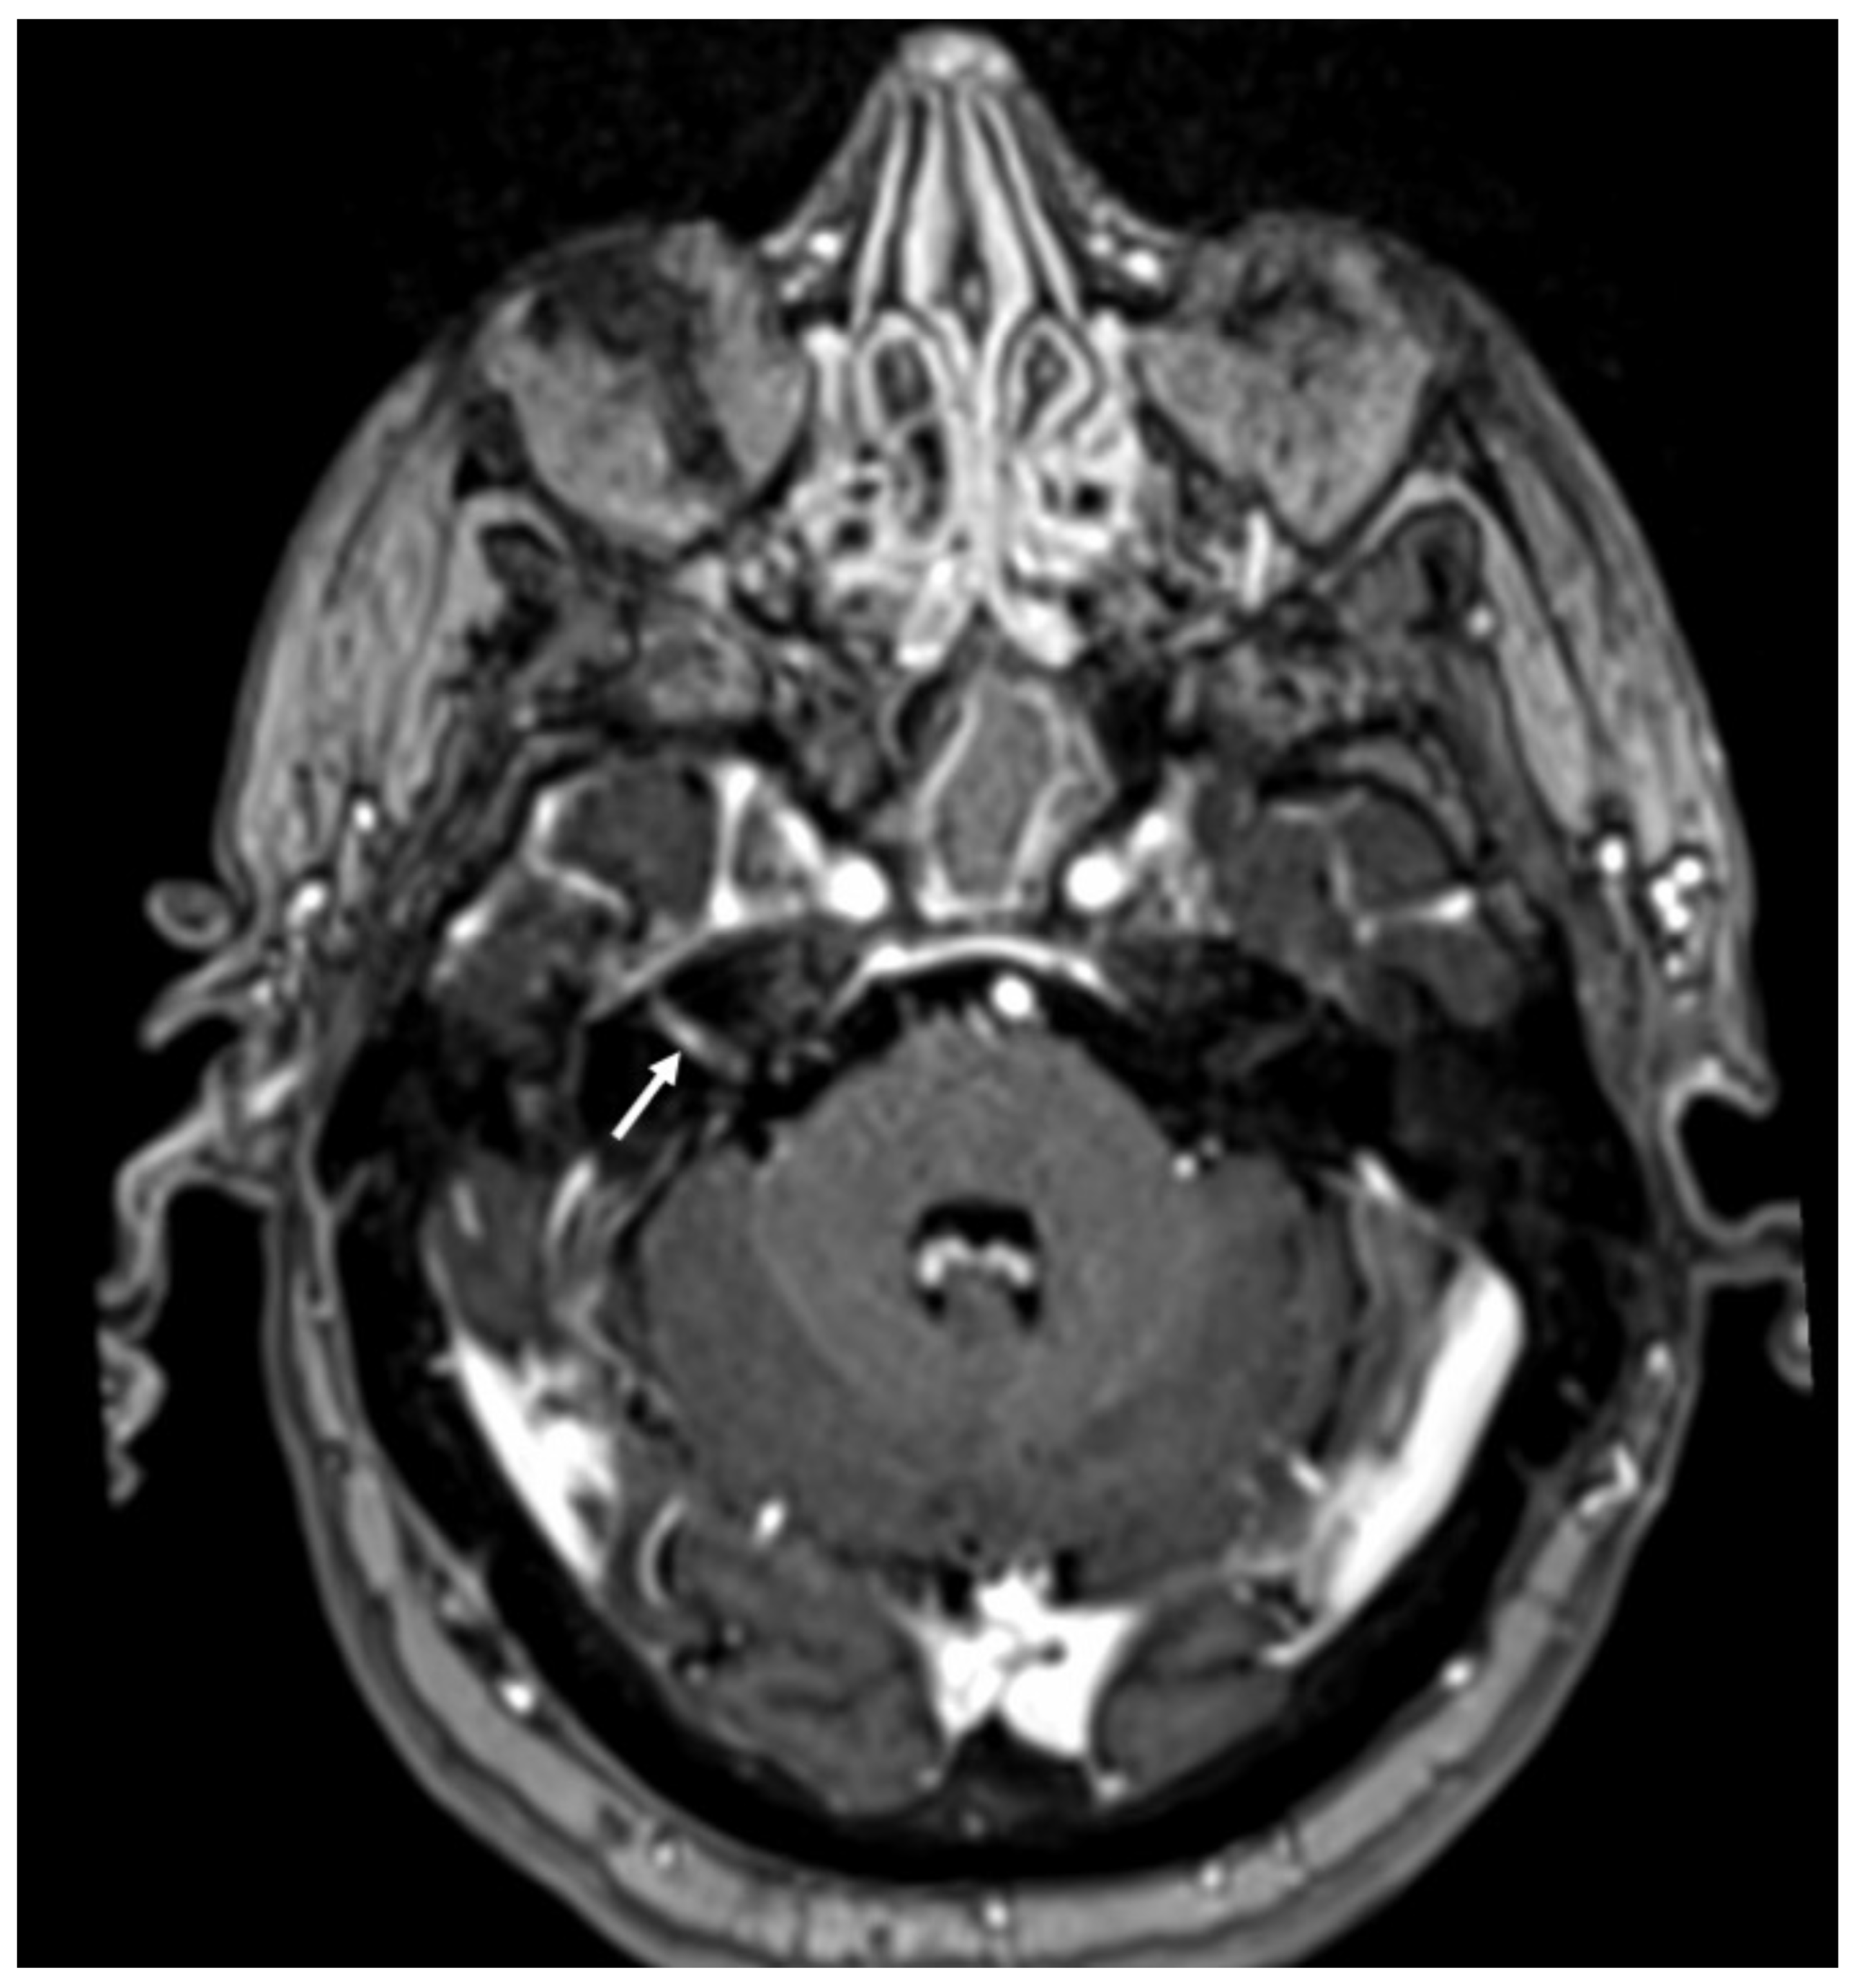

| Tuberculosis | • Leptomeningeal enhancement in the basal cisterns • Hydrocephalus very common • Infarcts in the basal ganglia due to vasculitis • Possible concomitant tuberculomas or miliary tuberculosis |

3. Tuberculous Meningitis/Meningoencephalitis